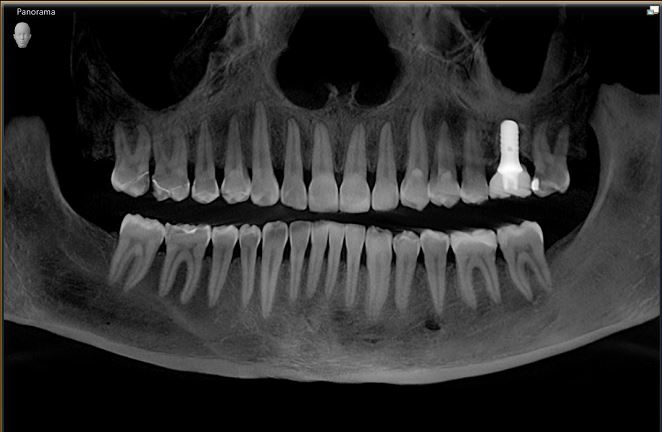

3D imaging, or Cone Beam Computed Tomography (CBCT), is a medical imaging technique that uses X-rays to create a 3D rendering of the maxillary and mandibular jaws, including the TMJ in most cases. For the first time, we are able to see bone, teeth, and sinuses in three different planes.